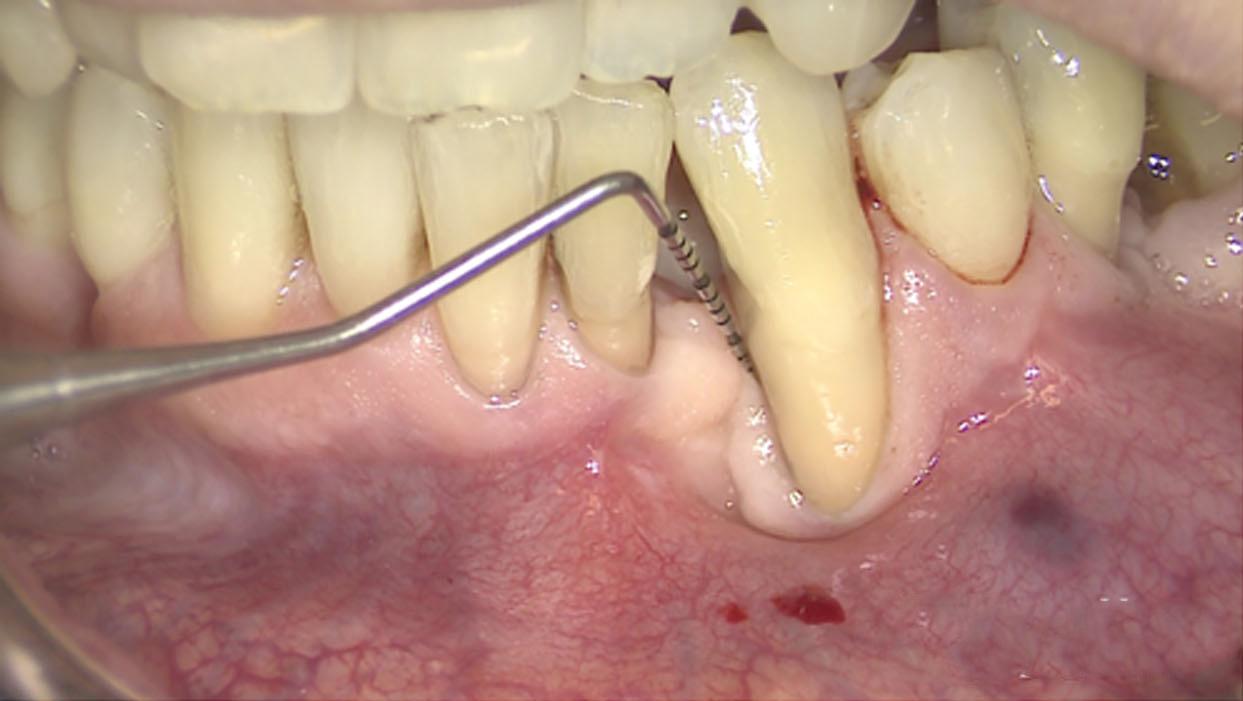

Fig 3. A 3D printed scaffold was designed using CAD software to fit a peri-osseous defect in a human patient. The scaffold consisted of a region with channels designed to support oriented PDL tissue formation and a region for the regeneration of osseous tissue. Fig 3: baseline;

Fig 4: defect model; Fig 5 through Fig 7: internal, tilted, and side views of scaffold, respectively; Fig 8 through Fig 10: coronal, middle, and apical

angles, respectively; Fig 11: cross-section diagram; Fig 12: labial scan image. (Images reprinted with permission from Rasperini G, Pilipchuk SP, Flanagan CL, et al. J Dent Res. 2015;94[9 suppl]:153S-157S.)

Fig 13. The scaffold was placed in the defect, where it remained for approximately 1 year. Fig 13: baseline; Fig 14: defect; Fig 15: scaffold matrix; Fig 16: scaffold placement; Fig 17: wound closure; Fig 18 through Fig 20: 2-month, 6-month, and 1-year postoperative, respectively. (Images reprinted with permission from Rasperini G, Pilipchuk SP, Flanagan CL, et al. J Dent Res. 2015;94[9 suppl]:153S-157S.)

Figure 13

Fig 14. The scaffold was placed in the defect, where it remained for approximately 1 year. Fig 13: baseline; Fig 14: defect; Fig 15: scaffold matrix; Fig 16: scaffold placement; Fig 17: wound closure; Fig 18 through Fig 20: 2-month, 6-month, and 1-year postoperative, respectively. (Images reprinted with permission from Rasperini G, Pilipchuk SP, Flanagan CL, et al. J Dent Res. 2015;94[9 suppl]:153S-157S.)